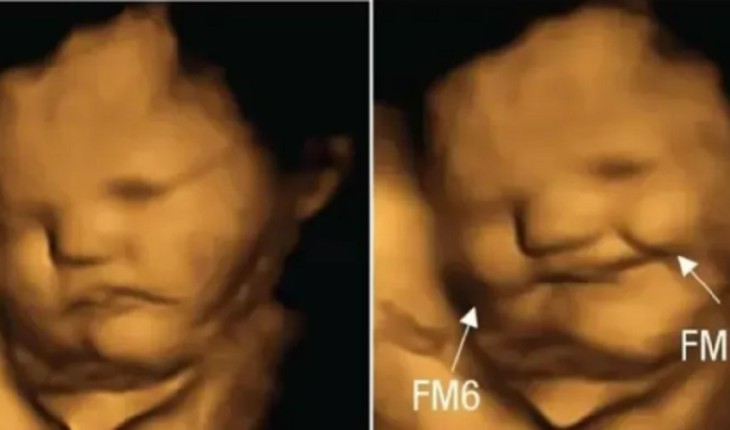

Uma pesquisa realizada recentemente mostrou reações dos fetos em tempo real.